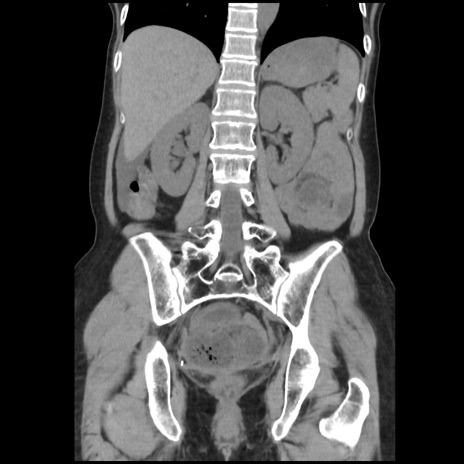

症例32(冠状断像)

【症例】40歳代 女性

【主訴】上腹部痛、嘔気・嘔吐

【現病歴】約9時間前頃から急に上腹部痛、嘔気、嘔吐が出現。改善しないため救急要請。

【既往歴】子宮頚癌(広汎子宮全摘術、放射線療法)、腸閉塞

【身体所見】腹部:平坦、軟、腸雑音亢進、上腹部を中心に腹部全体に圧痛あり。

【データ】WBC 8400、CRP 0.03